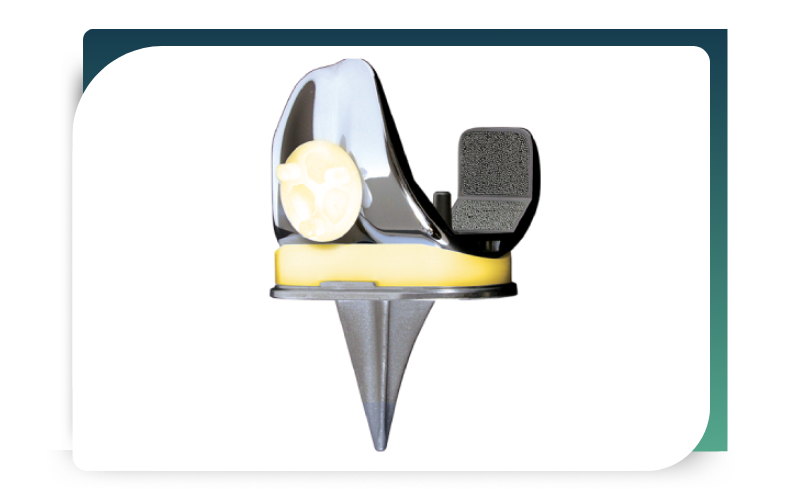

Advanced Robotic Knee Replacement – TUKSplasty